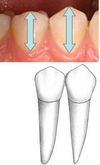

Maxillary buccal view: crown symmetry

Greater symmetry on maxillary 2nd premolar

Maxillary buccal view: occlusal-cervical dimension

Larger on maxillary 1st premolar

Maxillary buccal view: cervical width

Wider cervical neck on maxillary 2nd premolar

Maxillary buccal view: buccal cusp sharpness

Sharper on maxillary 1st premolar

Maxillary buccal view: buccal cusp ridge lengths

Mesial cusp ridge on maxillary 1st premoler is longer

Mesial cusp ridge on maxillary 2nd premolar is shorter